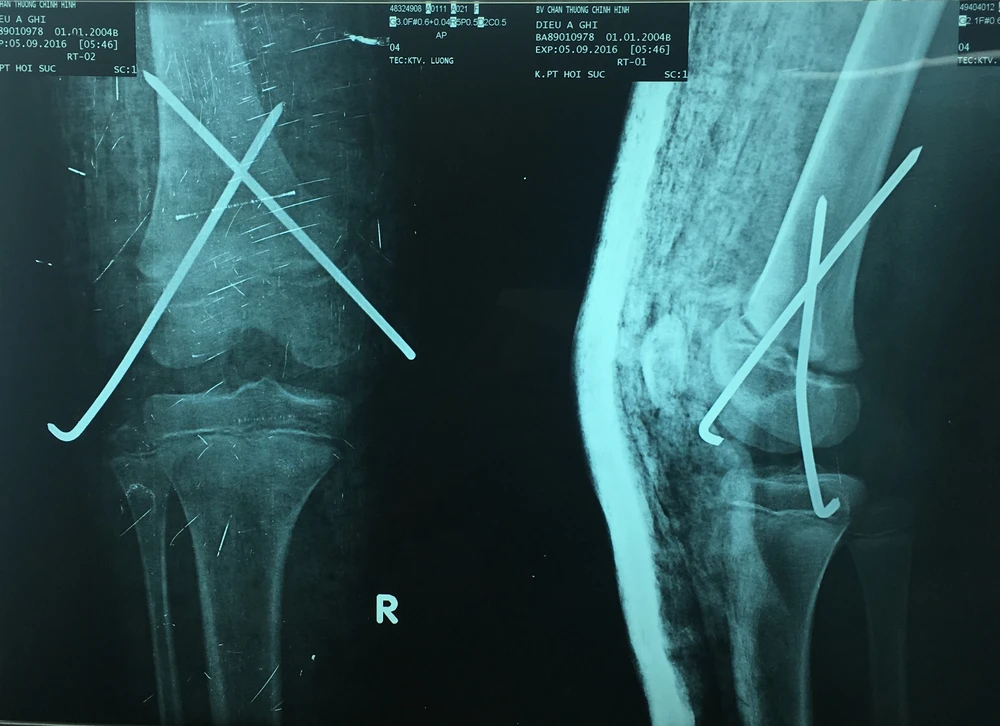

Bệnh nhi được kéo nắn kín dưới màn tăng sáng và xuyên chéo ba đinh để cố định xương gãy. Ảnh: HÒA KHÁNH

BS Đậu Thế Canh (khoa Chỉnh hình nhi) kéo nắn kín dưới màn tăng sáng và xuyên chéo ba đinh để cố định xương gãy.